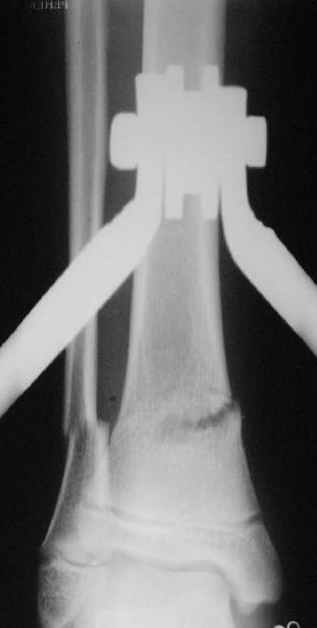

Нашел в комп-ре схожий случай:

1) з/репозиция, 2) фиксация 2 спицами, 3) аппарат, 4) фиксационные

спицы удалены...

См. аттачт.

А можно было наложить аппарат и по поводу ложного сустава...

По крайней мере не было бы укорочения (пусть и в 2 см)...